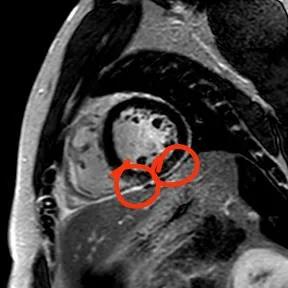

“快!做磁共振觀察心肌有無受損及程度?!庇跋裨\療中心陳寶瑩副主任為小燁進行心臟磁共振平掃及增強掃描。結(jié)果提示:患者有急性心肌損傷,考慮心肌梗死。結(jié)果驗證了小燁的心肌大片區(qū)失活。